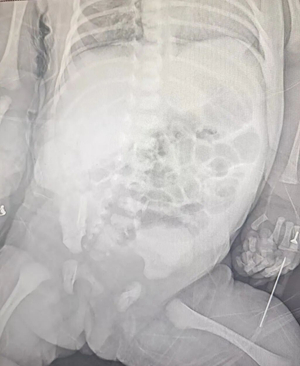

△腹部影像提示隐蔽性腹部出血